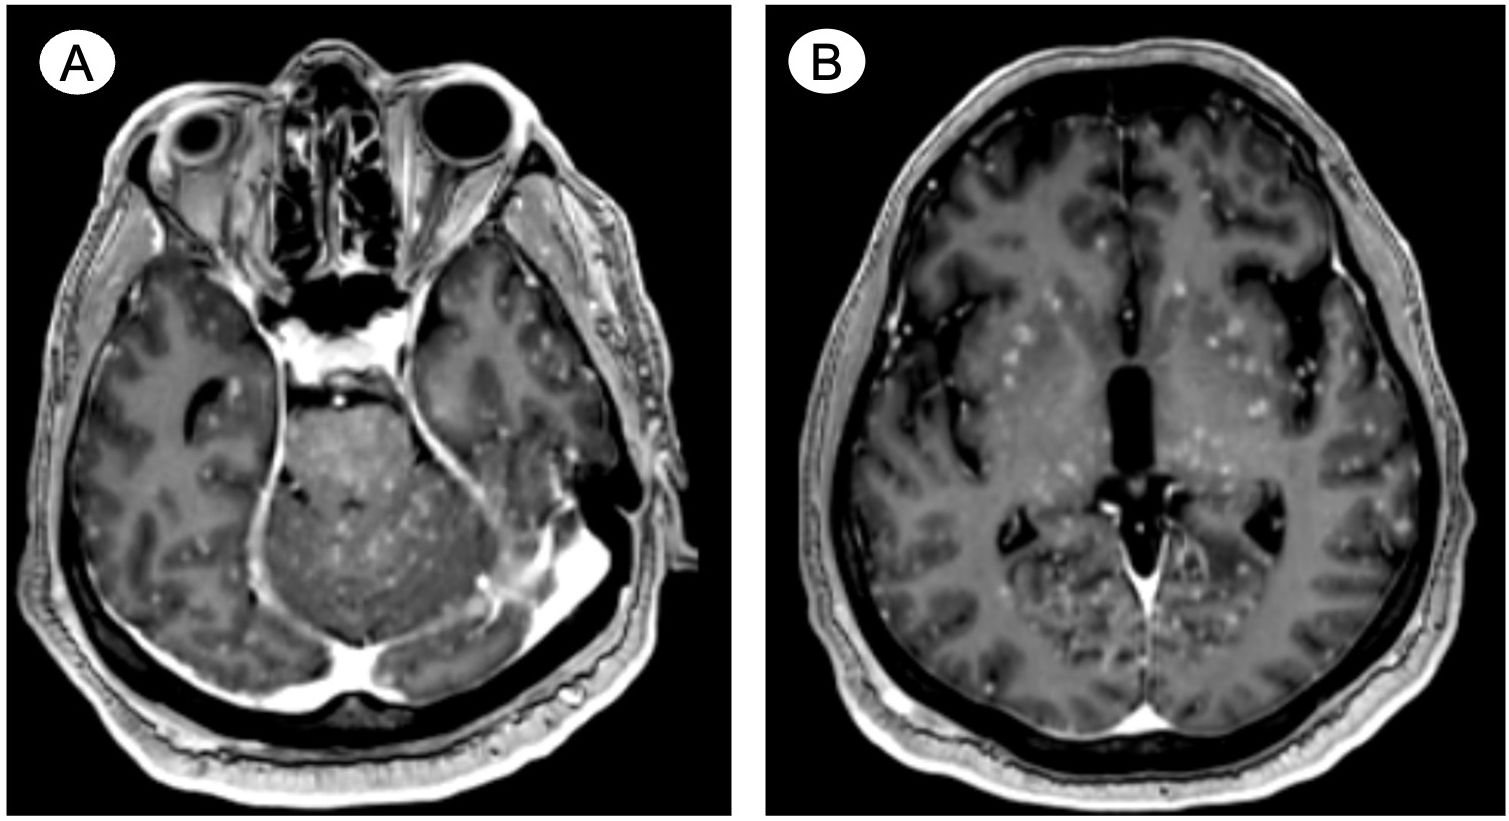

Introduction: Miliary brain metastasis (MM), consisting of innumerable miliary lesions in perivascular location, is a rare disease entity with an estimated incidence of 3.8% among patients with brain metastasis (BM). Similarly, with an approximated incidence of less than 2%, prostate cancer (PC)-related BM is also an infrequent presentation; however, it is more common in patients with neuroendocrine differentiation. To the best of our knowledge, one other case of MM secondary to PC has been reported. This case report discusses two additional cases of PC-related MM, a condition otherwise predominately observed secondary to pulmonary adenocarcinoma. Case Presentations: The first case describes a patient in his 60s known for metastatic PC with suspected neuroendocrine differentiation presenting with musculoskeletal pain, lethargy, and status epilepticus. Contrast-enhanced computer tomography (CT) angiogram and magnetic resonance imaging (MRI) of the head and neck revealed diffuse and innumerable foci in the cerebral hemispheres, brainstem, and cerebellum. The second case discusses a similarly aged male with biopsy-proven de novo mixed adenocarcinoma/small cell neuroendocrine PC and symptoms consisting of significant weakness, aphasia, confusion, and decreased level of consciousness. Non-contrast-enhanced CT imaging of the brain did not reveal MM; however, a follow-up contrast-enhanced MRI detailed miliary lesions in the cortex, white matter, deep gray nuclei, brainstem, and cerebellum. Both patients expired within a couple of weeks from admission. Conclusion: Given its rarity, notably in patients with PC, there are no specific and established diagnostic criteria for MM, a condition with ominous prognosis seemingly related to neuroendocrine differentiation in men with PC.